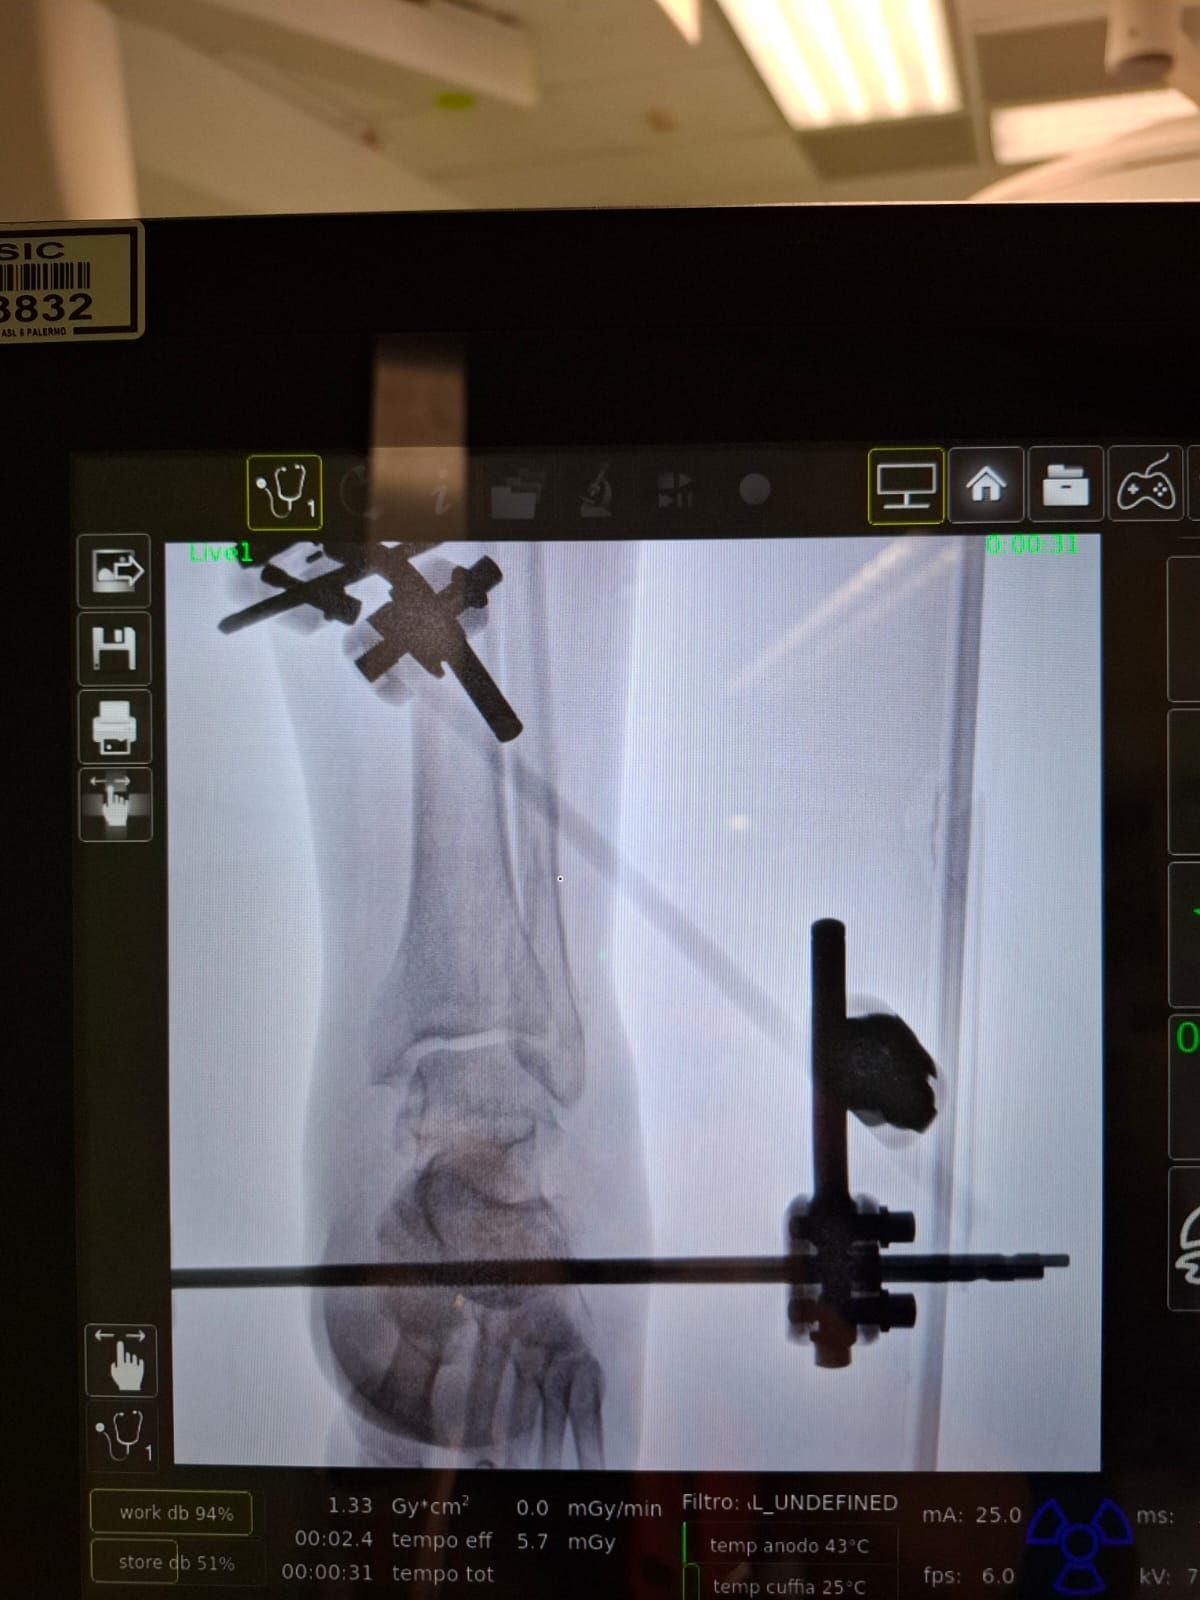

Foto e video